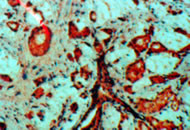

Лекция: "Прогностические факторы при раке предстательной железы".

Гистологический вариант